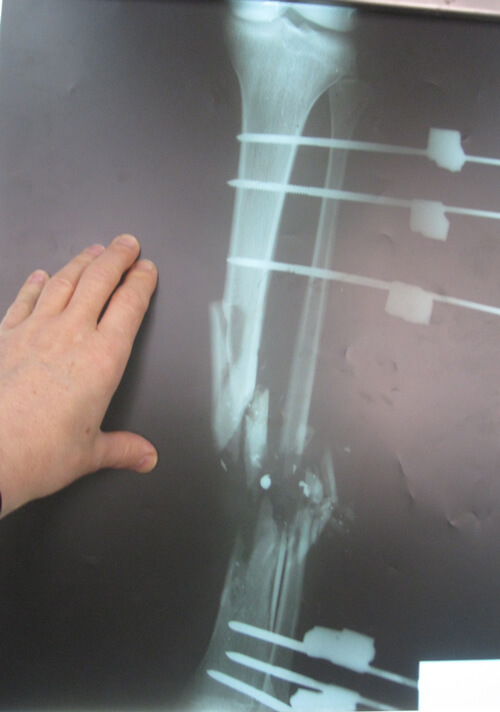

A 20-year-old man presented 46 days after a GSW injury to his right leg. He sustained a Gustilo IIIc fracture of the proximal tibia and fibula with division of the popliteal artery (Figures 13 & 14). The vascular defect was bridged acutely with a vein graft by a vascular surgeon. All toes were necrotic from either acute ischaemia or embolic injury. All compartments below the knee had been affected during the acute ischaemic episode. There was no neural function below the knee: the patient had an insensate foot with a pressure sore on the heel. This equated to a poor foot on an ‘almost dead’ stick.

Figure 13: Right lower leg following compound fracture and vascular injury. The sponge of a vacuum

assisted closure system is still in situ. Extension of the medial wound for access during

acute vascular repair as well as to allow extension as a medial fasciotomy.

Figure 14: Bone loss in the proximal tibial metaphysis.